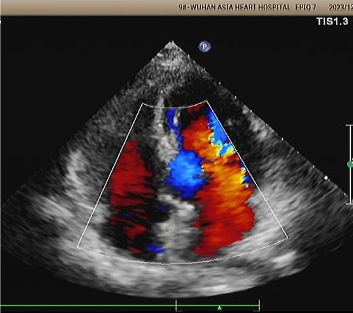

Имплантат: 2424 мемосорб®Биоразлагаемый окклюдер PFO, развернутый под руководством эха и DSA.

День 1-9 месяцев:

Остаточный шунт не наблюдается.